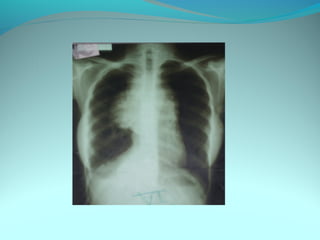

Opacité latéro_trachiale et hilaire droite grossierement arrondie de

6cm de diam dense et homogene

 la limite interne se confend avec le mediastin et la limite externe

nette convexe vers le mediastin

elle confond avec le mediastin évoquant une image mediastinale

Par ailleur on note:

Une surrélevation de la coupole diaph

Un coblement …..

DIAGNOSTIC:

Lymphome H ou NH

Volumineuse ADP tuberculeuse ou sarcoidosique